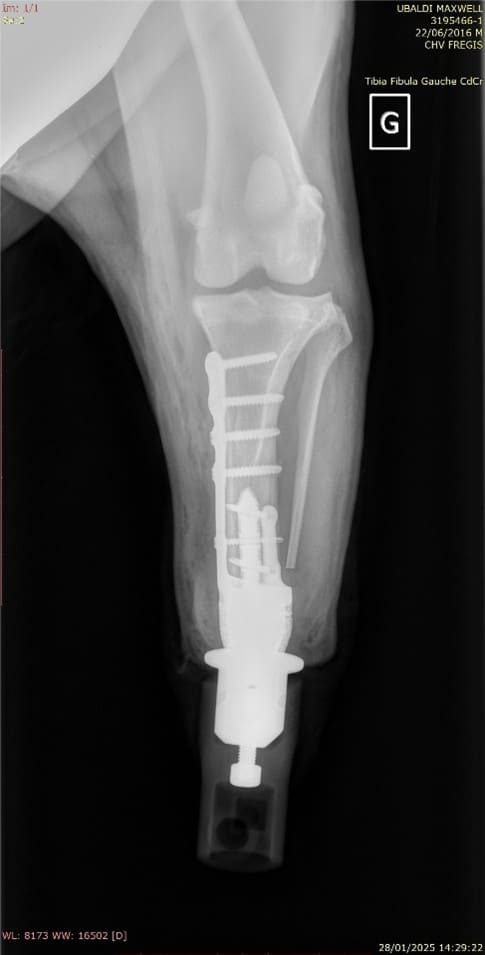

Maxwell est un chien Golden Retriever de 9 ans présenté en consultation d’orthopédie pour une boiterie du membre pelvien gauche évoluant depuis 2 semaines ainsi qu’une tuméfaction du tarse évoluant depuis 8 mois, dans un contexte d’arthrose évoluant depuis plusieurs années sur les autres membres. Il présente comme comorbidité une hypothyroïdie stabilisée médicalement avec de la lévothyroxine. L’examen orthopédique révèle une tuméfaction ferme et inconfortable à la manipulation du tarse gauche en faveur d’un processus tumoral ou dégénératif prioritairement. Le scanner suggère une prolifération d’atténuation tissulaire en périphérie de l’articulation tibio-talienne et les biopsies confirment un processus néoplasique de type sarcome des tissus mous (schwanome plus précisément). La prise en charge thérapeutique de choix a été ici la réalisation d’une prothèse d’amputation.

La prothèse d’amputation est un implant de conception unique intégrant deux parties : une endoprothèse (prothèse qui se fixe dans l’os et traverse la peau) et une exoprothèse (prothèse amovible se fixant sur l’endoprothèse qui permet l’appui).

Chaque exoprothèse est faite sur mesure par des ingénieurs biomédicaux après réalisation d’un scanner afin de s’adapter parfaitement à la taille, au poids et à la démarche naturelle de chaque patient. Au fil du temps, la base en caoutchouc de l’exoprothèse s’use comme la semelle d’une chaussure. Lorsque cela se produit, il suffit de détacher l’exoprothèse de l’endoprothèse et de la remplacer par un pied neuf.

Elle est indiquée seulement pour des lésions distales des membres, à partir du radius distal et du tibia distal. Elle peut être utilisée dans des circonstances de traumatisme, de tumeur ou déformation, dès l’instant que l’os de support de la prothèse est sain (non tumoral et non infecté).